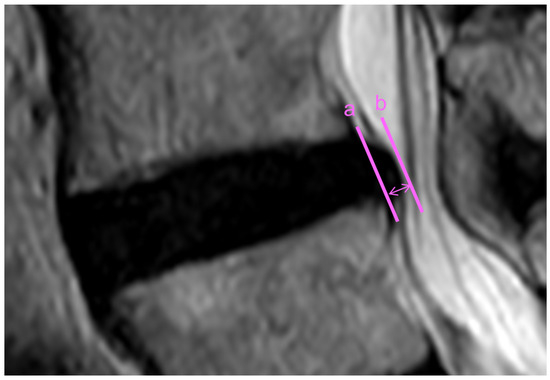

2.3. Magnetic Resonance Imaging Evaluation